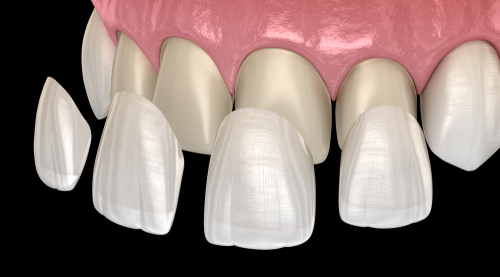

מהי אורתודונטיה אסתטית

בשנים האחרונות חלה עלייה במודעות לטפולים אורתודונטים אצל מבוגרים. הטפול האורתודונטי המסורתי בסמכים מתכתיים ("ברזלים") המורכבים על השיניים חודשים ואף שנים, מרתיע רבים המעוניינים בשיפור המראה האסטטי של שיניהם וחיוכם.

אורתודונטיה אסתטית למבוגרים

קיימות כיום מספר שיטות חדשניות ליישור שיניים במבוגרים שפותחו מתוך מודעות לחשיבות האסטטיקה לא רק בתום תהליך יישור השיניים אלא גם במהלכו והן מתאימות במיוחד לטיפול במבוגרים. השיטות כוללות סמכים שקופים המודבקים בחלק החיצוני של השיניים, סמכים בלתי נראים המודבקים בחלק הפנימי של השיניים (אורתודונטיה לינגוואלית) וקשתיות שקופות מסוגים שונים המורכבות על השיניים וניתנות להסרה.